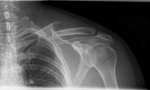

TAC Y RADIOGRAFÍA de los 15 días para que lo veáis.

Creéis que tiene lógica y tengo razón en lo que digo?

Se me olvidó deciros que en el informe pone rotura conminuta.

No soy médico ni un experto, pero en tu radiografía creo ver dos fracturas y eso suele ser cirugía. Conminuta es eso: trozos pequeños de hueso sueltos o daño a los tejidos alrededor, lo que suele bloquear los trozos de hueso e impiden que se alineen solos en una posición natural